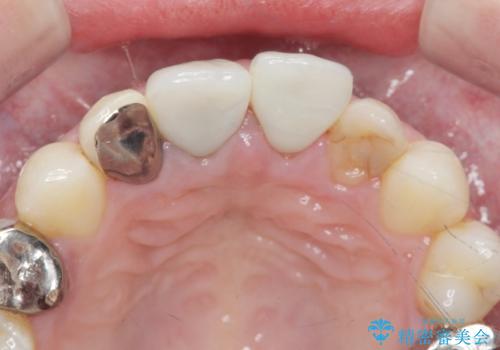

適合が良い被せ物が入りました。

前歯2本同時に行ったため色もピッタリで患者様に満足して頂けました。

被せ物と歯質に隙間があると細菌が入り込むために虫歯になるリスクが高くなります。